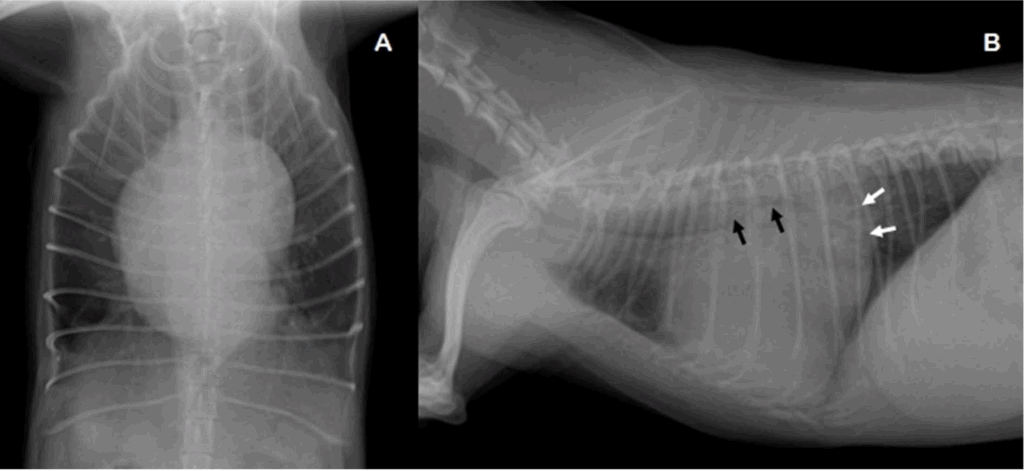

Fig 5. 증례 2의 흉부 방사선 사진입니다.

A: 배등 방향 촬영에서 좌심실과 좌심방 확장을 동반한 중등도의 심장비대가 관찰되었습니다.

B: 우측 측면 촬영에서 심한 좌심방 확장(흰색 화살표)과 기관의 등쪽 변위 및 기관지 압박(검은색 화살표)이 관찰되었습니다. 해당 환자는 심한 흉부 기관 허탈도 함께 동반하고 있었습니다.

(Thoracic radiography of the case 2. A: Ventrodorsal pro-jection of radiography showed moderate cardiomegaly with left ventricular and atrial dilation. B: Right lateral projection of radi-ography showed severe left atrial dilation (white arrows) and dor-sal displacement of trachea with bronchial compression (black arrows). The dog also had severe thoracic tracheal collapse. )